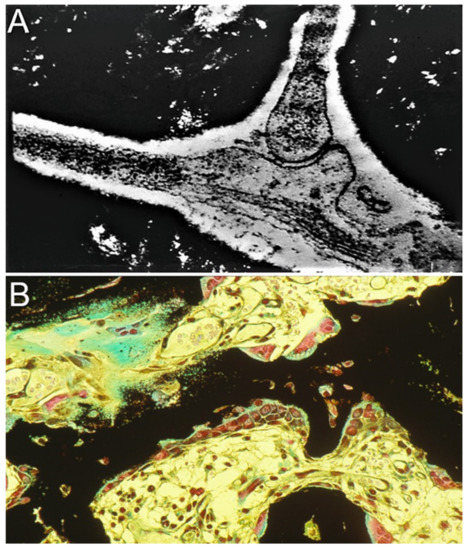

2.1. The Demineralized Bone Matrix-Induced Endochondral Bone Formation Model

2.2. Enhancement of Cell Differentiation in the DBM-EO Model by PEMFs

2.3. TGF-β Signaling under PEMF Stimulation in the DBM-EO Model